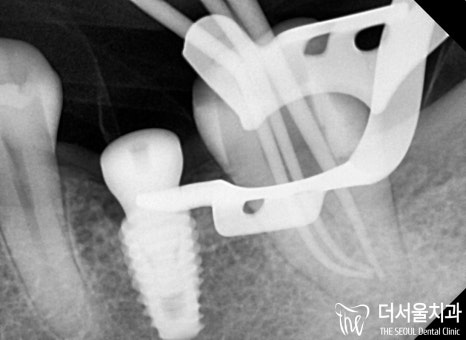

『누운 사랑니 발치 후, 우식 제거』

일단 문제가 되었던 누운 사랑니 부터

깔끔하게 뽑아주기로 하였습니다.

누운 사랑니 를 발치할 때에는

신경관이나 인접치들을 고려해야 된다는 거 알고 계시죠?

무엇보다 중요한 최. 소. 절. 개.로 진행했답니다.

이후 본격적으로 근관치료 과정을 진행했습니다.

감염된 근관을 제거한 다음

확장을 통해 좁아져 있는 곳을 넓혀줍니다.

이후 약제를 투입하여 병소를 제거하고

치과용 수복재를 뿌리 끝까지 채워 넣으면 되죠.

(이때 더서울에서 그렇게 강조했던

클램프와 러버댐, 꼭 사용해야겠죠?)